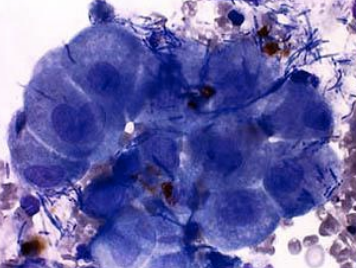

What cells on an FNA will have a round-ovoid nucleus, spindle-fusiform cytoplasm with a wispy tail, exfoliating cells and clumps, and are representative of sarcoma?

Epithelial

What cells on an FNA have a round nucleus, round-ovoid-angular cytoplasm with distinct borders, exfoliating cells in sheets and clumps, and can form ducts and acini? They are indicative of carcinoma and adenocarcinoma.

Round

What cells on an FNA have a round nucleus, round-scant-moderate cytoplasm, and exfoliative cells that are individual and discrete? They are indicative of plasma cell tumor, TVT, MCT, LSA, and histiocytoma.